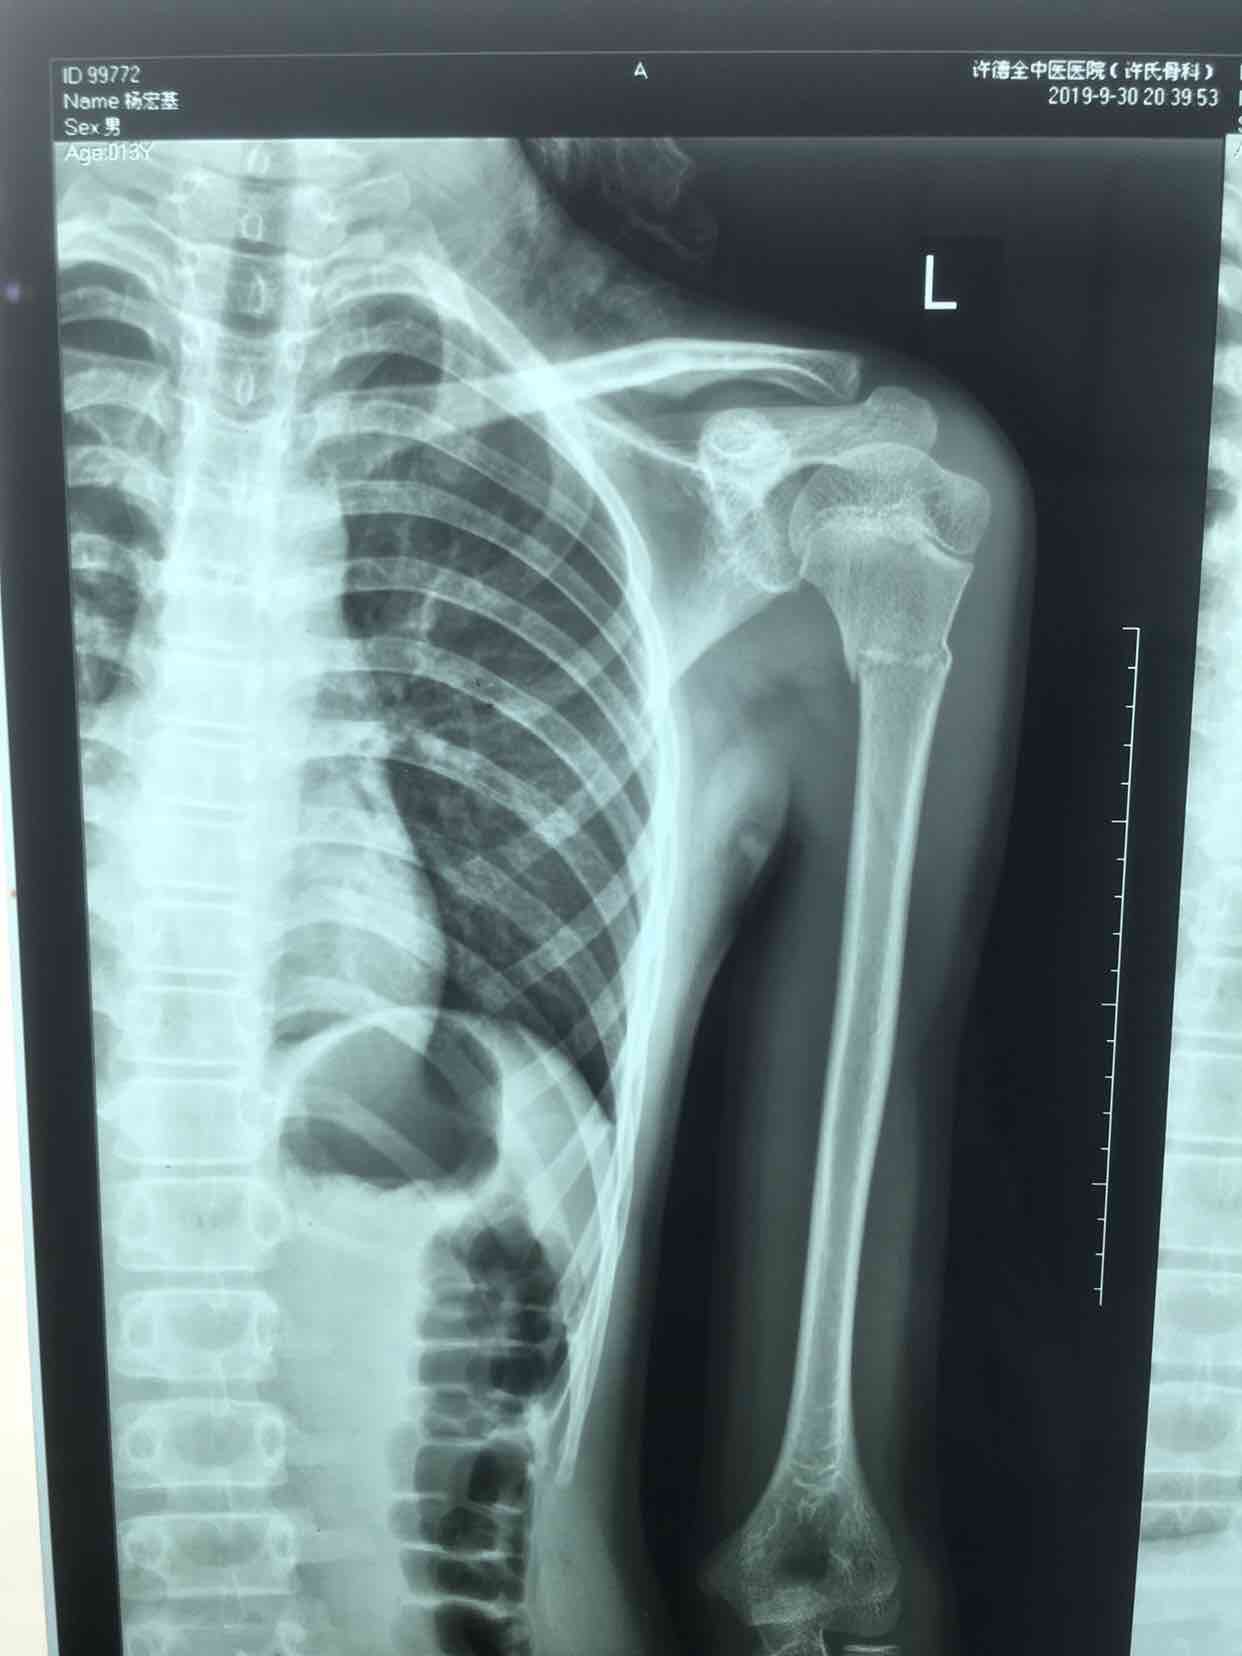

骨折 肱骨外科颈骨折

摔伤后左肩部肿痛,活动受限1小时入院。既往身体健康,无特殊不良嗜好。

生命体征平稳,心肺复未见异常。左肩部肿胀明显,局部皮色皮温正常,压痛及纵向叩击痛阳性,肩关节活动受限,末梢血运感觉正常。